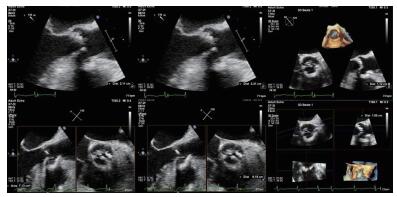

(1)经食道超声评估瓣环、窦、冠脉高度和升主动脉由于患者术前无法行CT检查,无法获知其主动脉根部情况,术中通过食道超声(2D和3D)评估主动脉根部结构。本病例术中经食道超声评估提示:主动脉瓣瓣环内径2.11 cm,主动脉窦部直径2.89 cm×2.84 cm×2.84 cm,右冠开口高度1.12 cm,左冠开口开口1.05 cm,升主动脉无明显增宽(图 3)。

| 图 3 患者术中经食道超声心动图 |